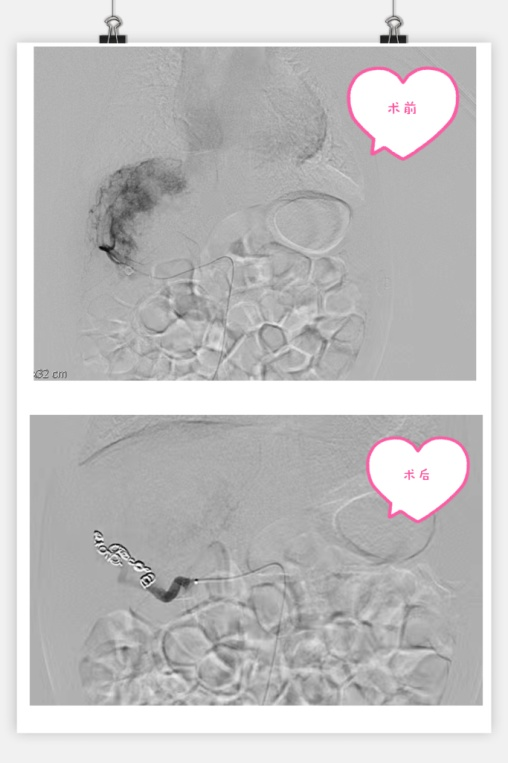

3月13日,在小儿外科高亚教授、郑百俊教授及郭新奎教授及多学科的积极配合下,为患儿进行了肝动脉造影术+肝动脉栓塞术。新生儿股动脉纤细,常规股动脉鞘作为入路存在术后股动脉闭塞下肢缺血风险,采用了经股动脉单纯微导管超选择性栓塞,手术难度大大增加,但避免了股动脉缺血风险。

在麻醉科(吴刚副主任,罗倩倩、陈趟医生)和新生儿科(王惠萍教授、王莉医生)的保驾护航下、超声科(何鑫医生)的精准定位置管,血管介入团队(彭玉萍教授、刘强教授、杨晓东医生)经过3小时的努力,共封堵四处肝血管瘤的主要供血动脉分支,手术过程患儿生命体征稳定,血管瘤的血流量逐渐减少,进行心功能测定显示心输出量较术前下降,效果显著,肝脏的“扫雷”行动获得阶段性的成功,在场的所有医务人员为孩子鼓掌加油!